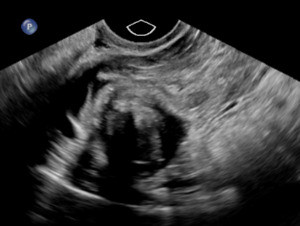

The patient was taken urgently to the operating room for diagnostic laparoscopy due to concern for right adnexal ectopic pregnancy. Upon entry into the abdomen, hemoperitoneum was noted extending into bilateral paracolic gutters. Following removal of this clot, a ruptured ectopic pregnancy was identified at the inferior pole of a 4 cm pedunculated fibroid arising from the posterior fundal surface of the uterus with active bleeding (Figure 2). This ectopic pregnancy revealed no involvement of bilateral adnexa. Pelvic survey revealed normal bilateral fallopian tubes and ovaries. The pedunculated fibroid and ectopic pregnancy were resected with the Ligasure impact device and removed from the abdomen by two separate Endocatch bags. The base of the myomectomy (Figure 3) was oversewn with 2-0 vicryl for additional hemostasis.